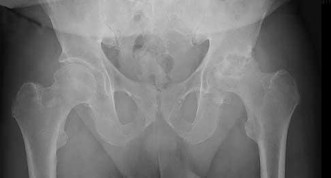

A 32-year-old male is brought to the trauma bay in hemorrhagic shock after a motorcycle crash. An anteroposterior radiograph of the pelvis demonstrates an APC-III injury. A pelvic binder is applied. To maximize reduction of the pelvic volume, at what anatomical landmark should the binder be centered?

Explanation:

Pelvic binders should be centered over the greater trochanters to effectively close the pelvic ring and reduce pelvic volume. Placement over the iliac crests or ASIS can paradoxically widen the true pelvis or fail to achieve adequate reduction in an open-book pelvic injury.